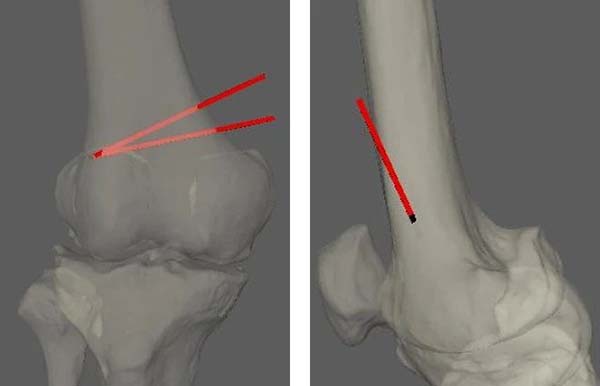

在完善术前准备后,手术于4月30日上午进行。术中个性化的3D导板,辅助术者在术中快速定位,通过透视确认导板安放位置、截骨方向、截骨线入点及合页位置等关键参数,均与术前规划完美契合。

术中X线与AI术前设计对比照片

与人工膝关节置换手术相比,截骨手术具有骨量损伤小、创伤小、运动功能恢复快等优势。同期开展关节镜探查,可根据实际情况实施软骨清理、半月板成形或缝合等操作,做到“内外兼修”。术前AI基于患者影像学数据,对其骨骼结构进行三维重建,并自动测量关键数据,完成力线调整、截骨位置、截骨角度和深度设定及钢板位置模拟等一系列工作,最终生成可视化的术前规划,以此为依据通过3D打印生成导板,引导手术,不仅提升了手术的精准性与效率,更从根本上推动了骨科诊疗模式的变革。